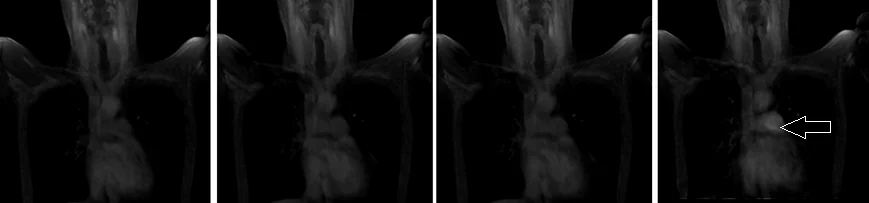

localiser arm down MRA and MRV of subclavians

A three-plane TrueFISP localizer must be taken initially to localize and plan the sequences. These are fast single-shot localizers with under 25s acquisition time, which are excellent for localizing vascular structures. Take at least 5-8 slices in all planes to get the best results.

mra subclavians localizer arm down - MRI